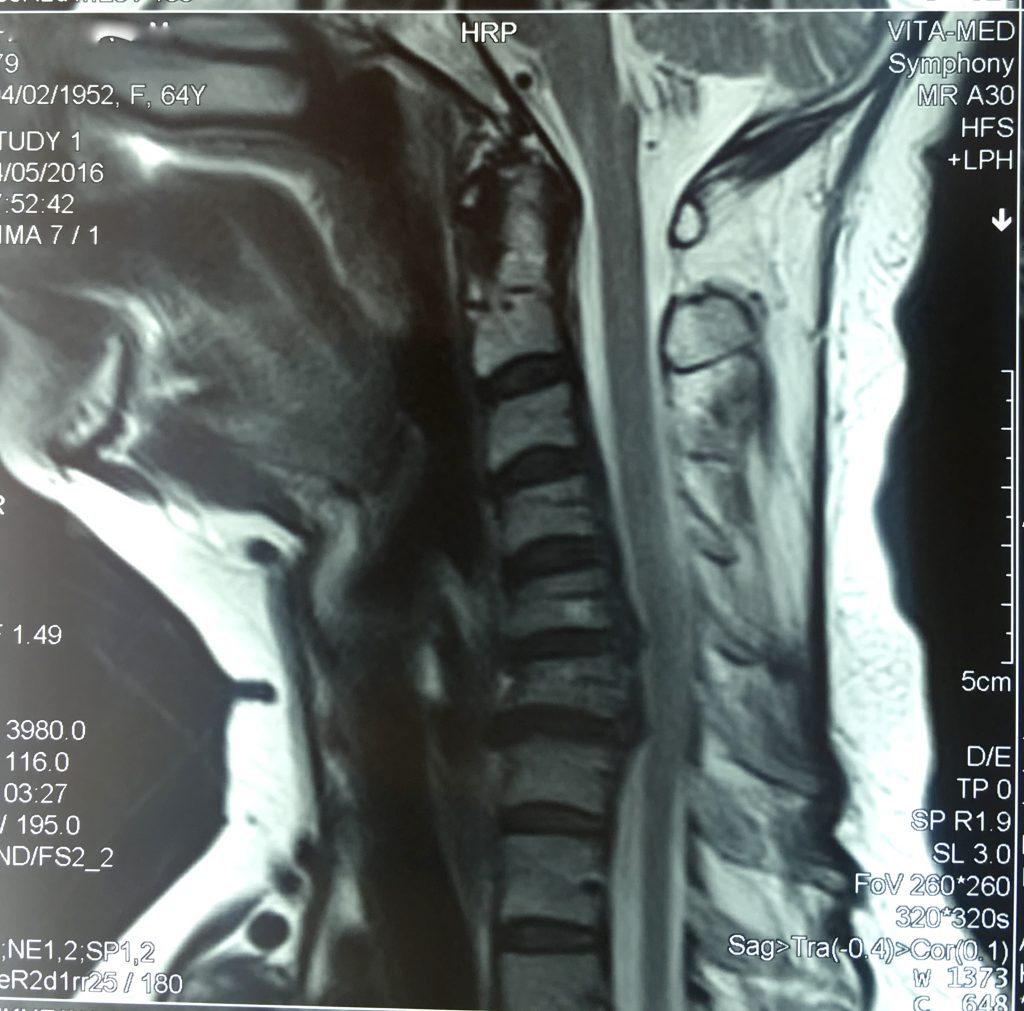

Симптоматична картина стенозу хребетного каналу поперекового відділу характеризується плавним наростанням. Стеноз хребетного каналу шийного відділу відрізняється різким погіршенням стану, що пов’язано зі здавленням у шийному відділі безпосередньо спинного мозку, а зменшення діаметра каналу призводить до негайних ускладнень.

Найчастіше у людини розвивається мієлопатія – вкрай тяжке ускладнення, яке характеризується порушенням чутливості в кінцівках та значним зниженням м’язової сили – тетрапарез, або у занедбаних випадках – тетраплегія.